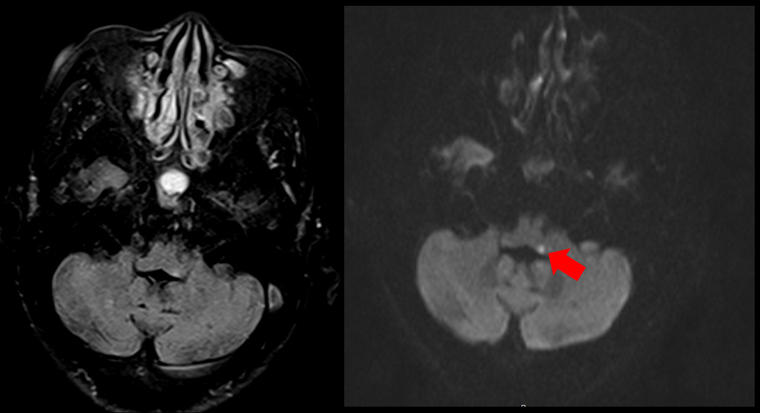

談到頭暈,朱海瑞醫師說明,暈眩分為「周邊型眩暈」以及「中樞型眩暈」,前者和耳部的前庭系統受影響有關,分為前庭神經炎、梅尼爾氏症,良性陣發性姿勢性眩暈等,這類型感到的是天旋地轉的暈,而中樞型眩暈最常見於小腦及腦幹中風患者,可能伴隨著腦中風典型狀況。朱海瑞醫師日前收治一名80歲有三高的婦人,某天起床時感到頭暈目眩,甚至想吐而就醫。因考量到婦人80歲的高齡還有心血管病史,因此會診神經內科,透過腦部核磁共振檢查,診斷老婦人是腦幹梗塞型中風。

▲透過腦部核磁共振檢查,箭頭處亮點為血管梗塞位置,醫師診斷老婦人是腦幹梗塞型中風。(圖/恩主公醫院提供)